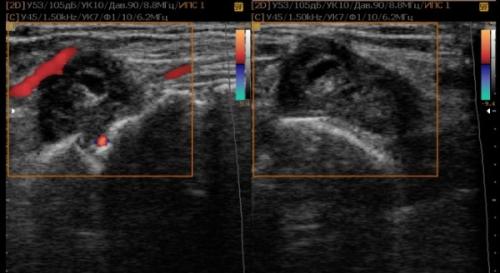

На втором этапе оценивают стабильность тазобедренного сустава сустава при пробе Барлоу-Ортолани. В нестабильном суставе костное покрытие головки уменьшается, а расстояние от лобковой кости до головки и ∠β увеличиваются.

На третьем этапе тазобедренный сустав сканируют в поперечной плоскости. В случаях нестабильности, подвывиха или вывиха определяют кпереди или кзади смещается головка при пробе Барлоу-Ортолани.

Когда головка смещается кнаружи, освободившееся пространство заполняет гиперэхогенная круглая связка и жир. При подвывихе и вывихе расстояние от лобковой кости до головки >6 мм, разница между бедрами >1,5 мм (3). Толстый хрящ лобковой кости считают вариантом нормы (4).